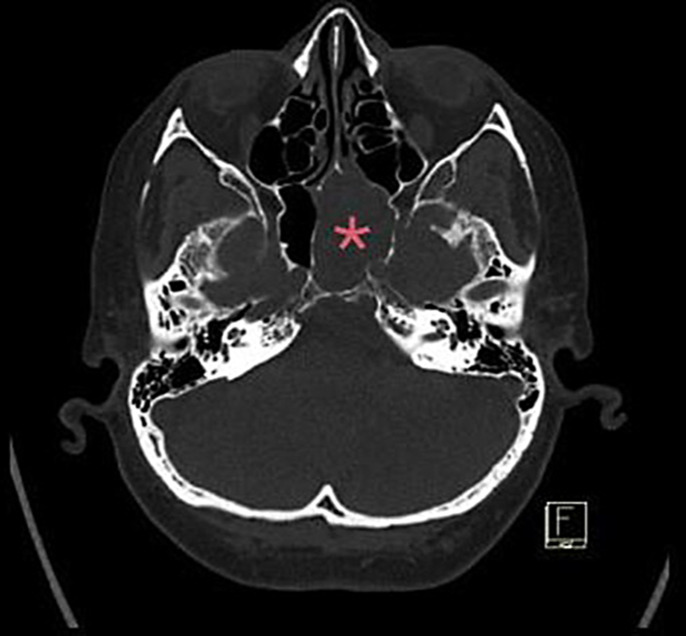

Case report: A 57-year-old woman with a history of infiltrative ductal carcinoma of the breast diagnosed 12 years earlier presented with progressive left-sided vision blurring and headaches for 3 weeks. Imaging revealed a heterogeneous lesion in the left sphenoid sinus compressing the optic nerve. The metastatic breast carcinoma with histopathological and immunohistochemical profiles matching the primary tumour was confirmed by biopsy. Because of the lesion's unresectable nature and additional metastases to the bones and lungs, palliative treatment was initiated, consisting of intensity-modulated radiation therapy and systemic therapy with abemaciclib and letrozole. After treatment, the patient's vision improved, and follow-up imaging showed reduced lesion size.